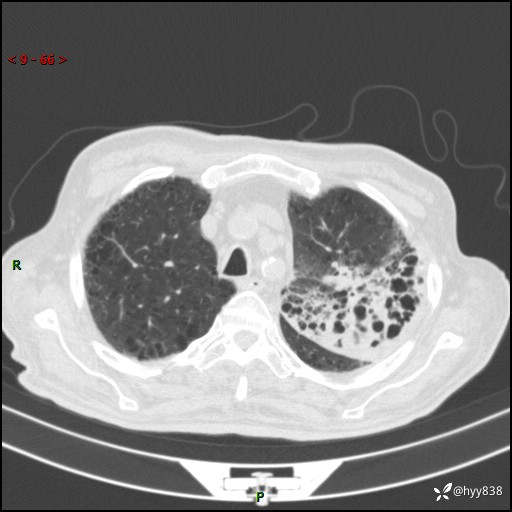

老年男性,间断咳嗽咳痰20余年,加重伴发热1天。呼吸科疑难病例讨论---结果公布

主诉:间断咳嗽咳痰20余年,加重伴发热1天

简要病史:家属代诉患者于20余年前无明显诱因出现咳嗽咳痰,痰为白色泡沫状,未行特殊治疗,不伴胸痛、胸闷、气喘、咳血等不适,1天前上午患者无明显出现发热,查体温39℃,伴咳嗽,咳痰无力,自行予以物理降温对症治疗,今晨2点左右再次出现发热,体温达40℃,自行服用复方氨酚烷胺对症治疗,凌晨3点左右复测体温38.2℃,现患者为求进一步诊治于今日就诊于我院门诊,行胸部CT提示双肺感染,遂以“肺部感染”收入我科。 患者本次起病来精神、食欲、睡眠欠佳,体力下降,体重无明显变化。

辅助检查:CT

胸部CT平扫